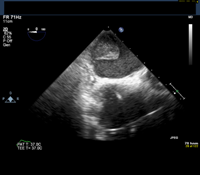

Given this history, the patient is scheduled for an elective transesophageal echocardiogram the day after presenting to the clinic. The images below show the TEE findings: a large 5.5-cm x 2.7-cm heterogeneous multilobulated mass, attached along the posterior wall of the left atrium, which likely represents a thrombus. (Click to enlarge the images.)